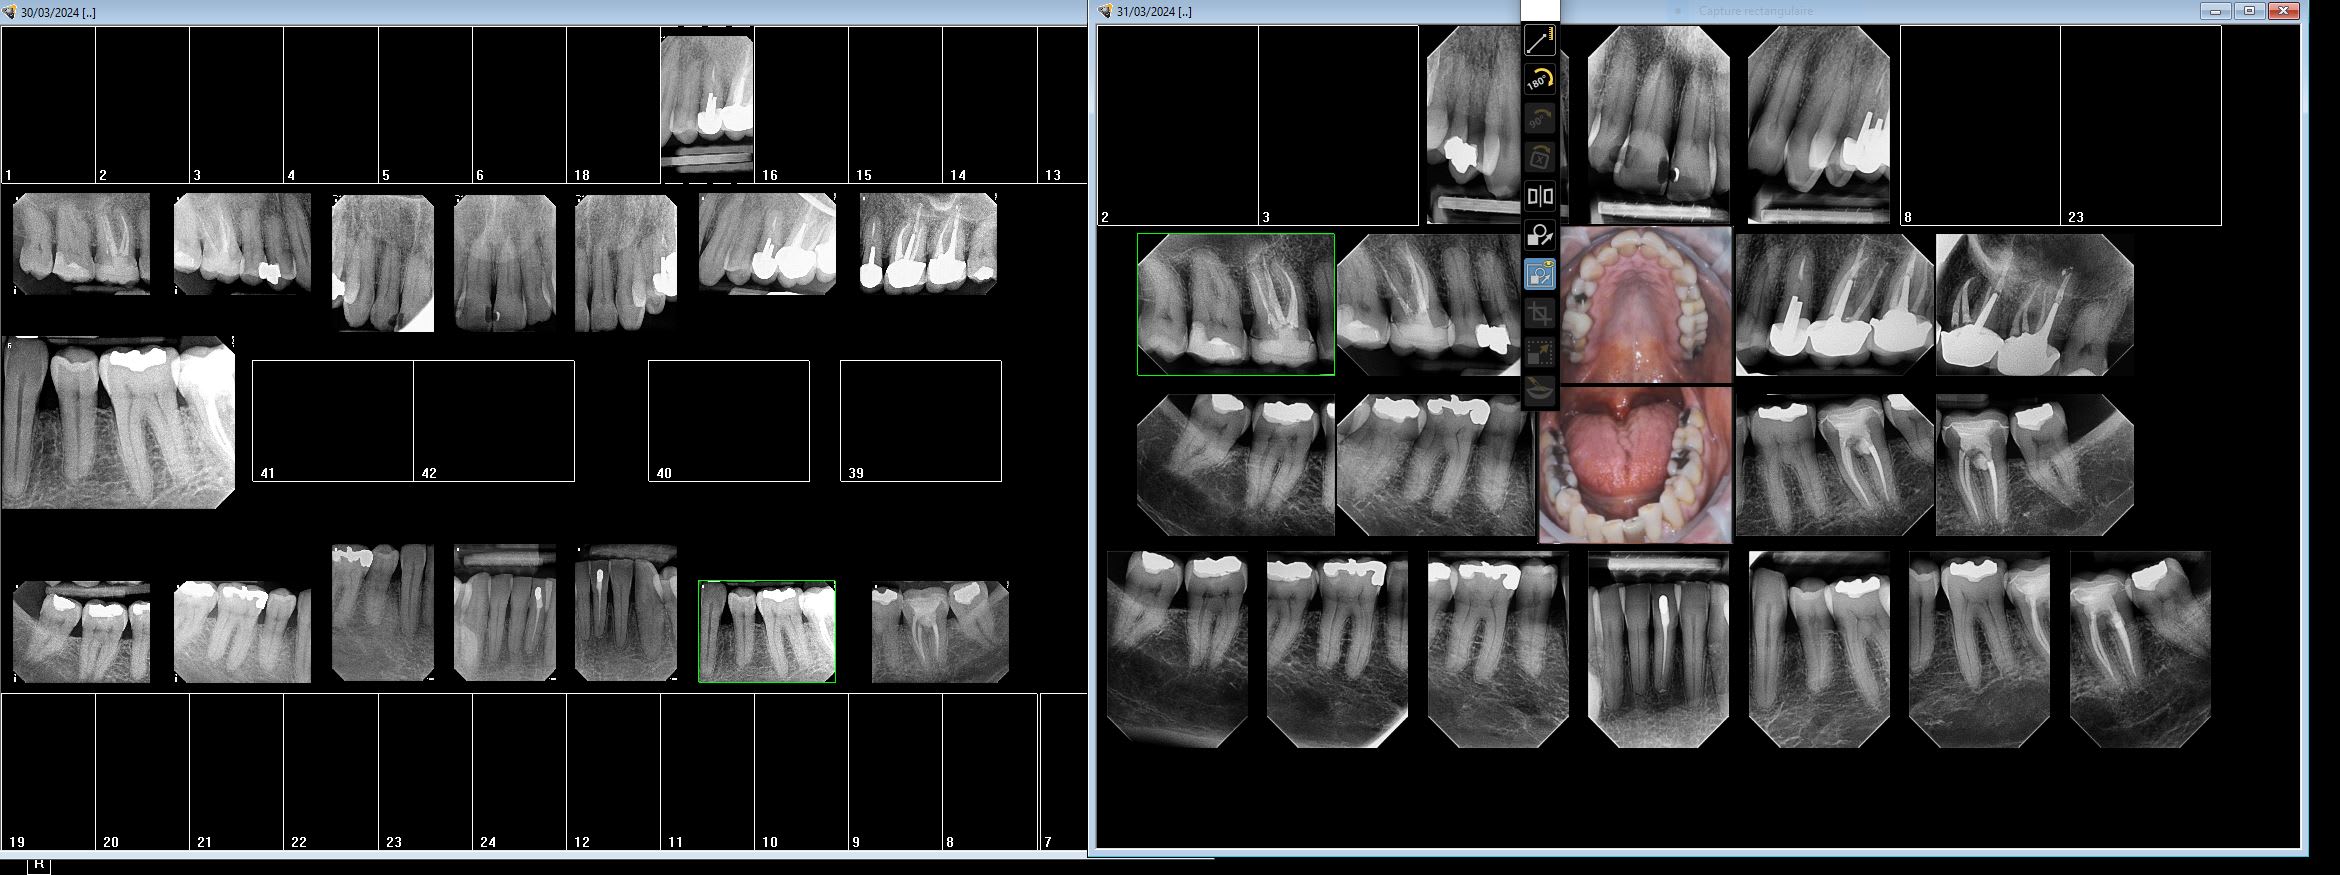

CS 6200 VS I sensor wood pecker

--

U1hmcyehazycn2ogu4ihlnk89fs9 - Eugenol

01/04/2024 à 05h55

Ztazqvfo0icuajk94i1s5e4ijsx6 - Eugenol

Cherchez l'erreur.